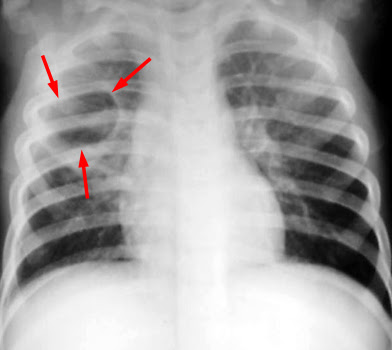

Pneumatocoeles form when the alveoli or lung tissue become inflamed and air-filled cavities develop due to the rupture of alveolar walls in severe pneumonia. This occurs when the inflammation causes a breakdown of the lung parenchyma, leading to trapped air and the formation of these cystic spaces.

Pneumoatoceles in CE CT chest

Characteristic feature of staphylococcal pneumonias.

• Cavitation (single or multiple thick walled cavities) may be bilateral.

• Pleural effusion/ Empyema with or without branchopleural fistulas (Pyopneumothorx).

• Abscess formation.

Pneumatocoeles are thin walled cystic spaces that may contain air fluid levels is the characteristic feature of staphylococcal pneumonias.